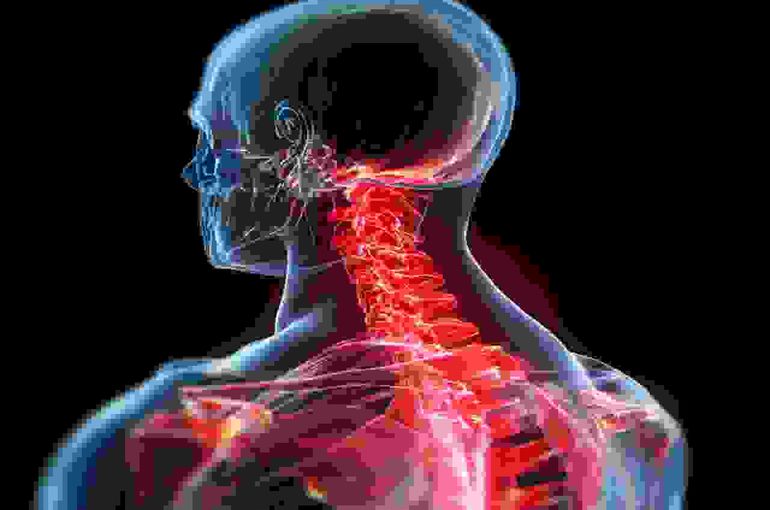

ストレートネックとは、本来緩やかなS字カーブを描いているはずの首の骨、すなわち頸椎が、何らかの原因によってその自然な湾曲を失い、まっすぐになってしまっている状態を指します。

正常な首の骨は、頭の重さを分散させるクッションのような役割を果たしています。しかし、ストレートネックになると、このクッション機能が失われ、頭の重さが首や肩の筋肉に直接かかってしまうため、様々な不調を引き起こしやすくなります。

ストレートネックによって引き起こされる症状は多岐にわたります。首がまっすぐになることで、首周りの筋肉や神経、血管に過度な負担がかかり、以下のような不調が現れることがあります。